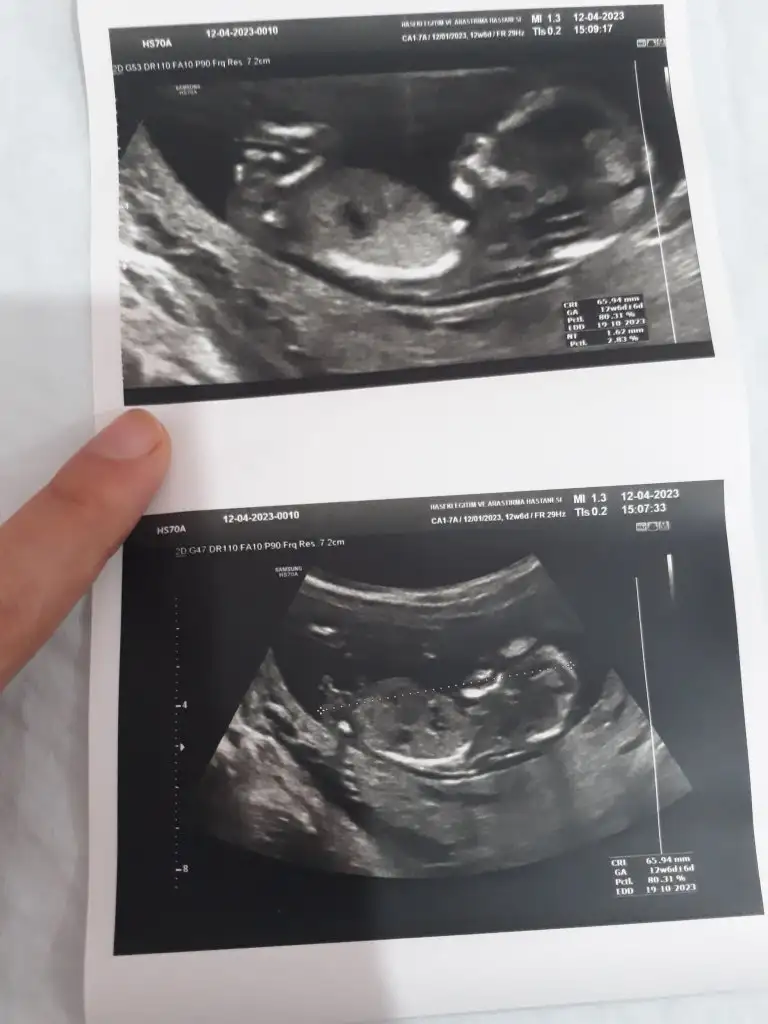

12 haftalık ultrasonu bu var mı tahmininiz

• 20230619_093856.webp

28,4 KB · Görüntüleme: 44